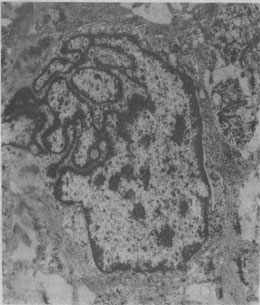

核碎裂(karyorrhexis):染色质逐渐边集于核膜内层,形成较大的高电子密度的染色质团块(图1-2)。核膜起初尚保持完整,以后乃在多处发生断裂,核逐渐变小,最后裂解为若干致密浓染的碎片。

图中央为一巨大的细胞核,核膜曲折凹陷,使核呈奇异形(纤维肉的电镜照片)